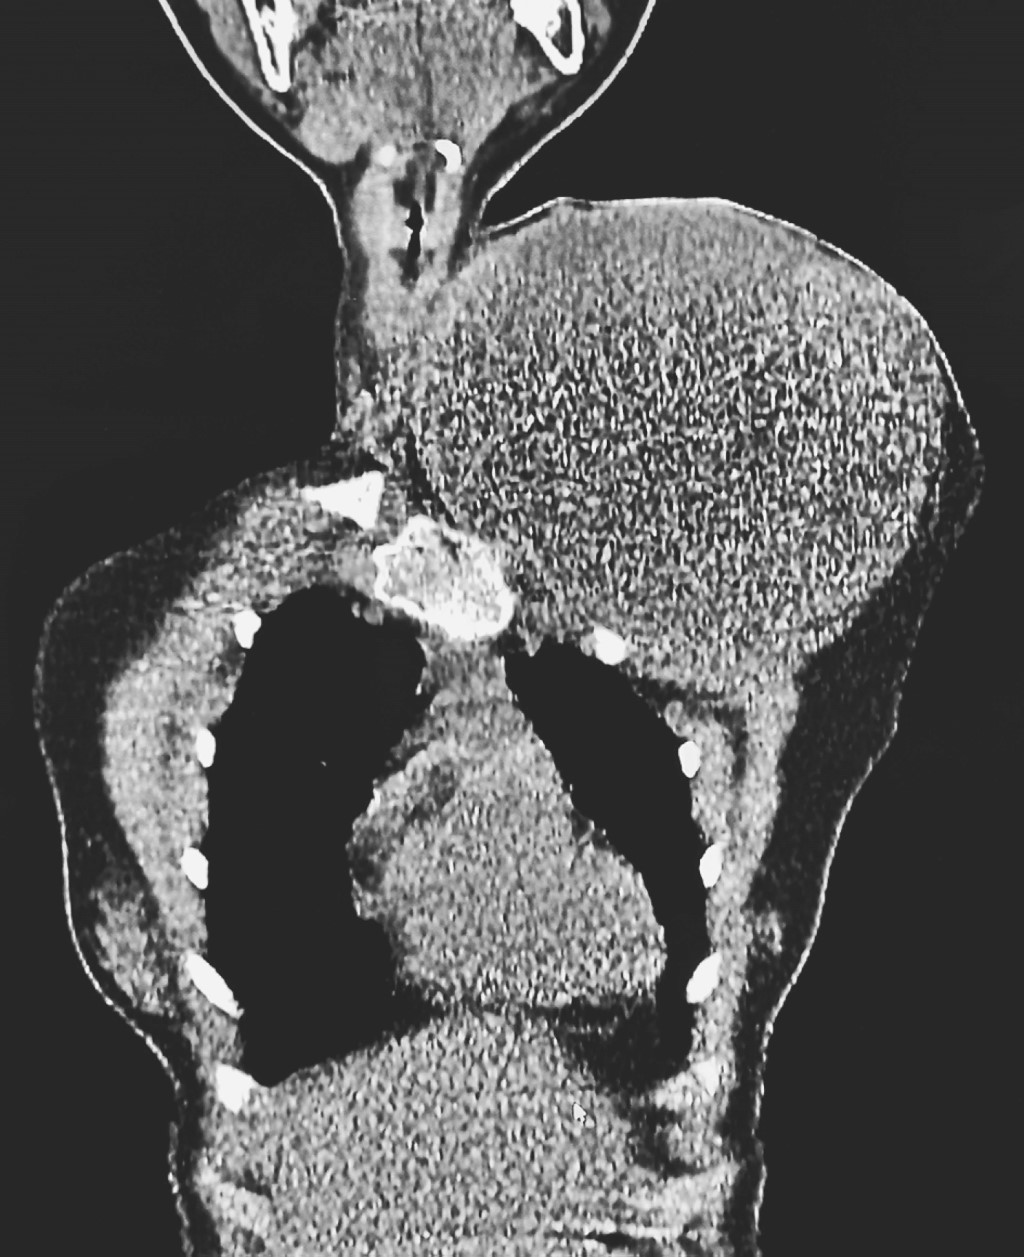

By conventional radiology, the absence of the clavicle was observed with its replacement by a soft tissue mass with neoplastic characteristics. Computer tomography (Figures 1 and 2) and magnetic resonance imaging (Figure 3) show a neoplastic lesion which replaces the left clavicle and generates compression and vascular displacement. No evidence of sternal and/or acromial involvement is seen. The lesion rests on the first and second left ribs, however tumor involvement of it is not proven due to continuity. Both studies showed tracheal and thyroid shift to the right and the neurovascular structures of the neck (internal and external jugular veins, subclavian vein, common carotid artery and brachial plexus) are shown compressed and displaced. By magnetic resonance imaging, T1-weighted sequences showed isointensity to muscle, and T2-weighted sequences showed heterogeneous hyperintensity (Figure 3).

Figure 1

Figure 2